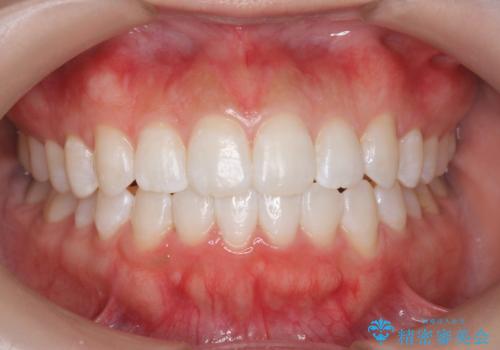

オフィスホワイトニング(エクセレントコース)

- オフィスホワイトニング希望で1日で白くしたいとのことでした。

オフィスホワイトニングのエクセレントコース(¥29700)を行いました。

- ¥29700費用は治療当時の料金となります